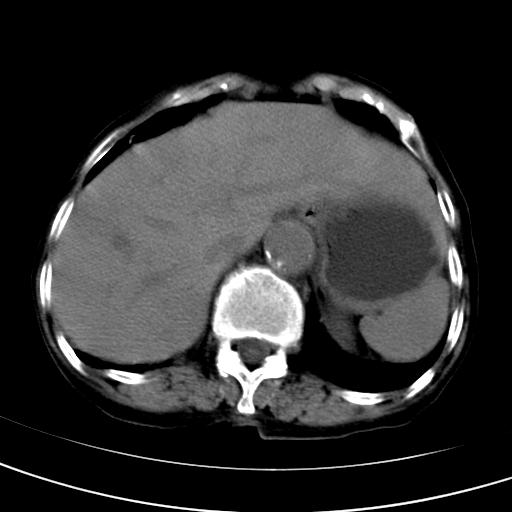

以下是引用wolft在2008-3-5 12:30:00的发言:[br]肝脏未见明显肿块影,但肝左叶增大,跨越腹中线到达脾胃前,且有一血管过去,考虑为先天变异:獭尾肝,胆囊为慢性胆囊炎急发,但胰腺头颈部有增大,密度不均匀,应该ct增强一下。

以下是引用zjzjr在2008-3-5 16:41:00的发言:[br]1.考虑慢性胰腺炎急性发作,建议增强除外占位性病变.[br]2.胆囊结石伴胆囊炎.[br]3.肝内胆管结石.